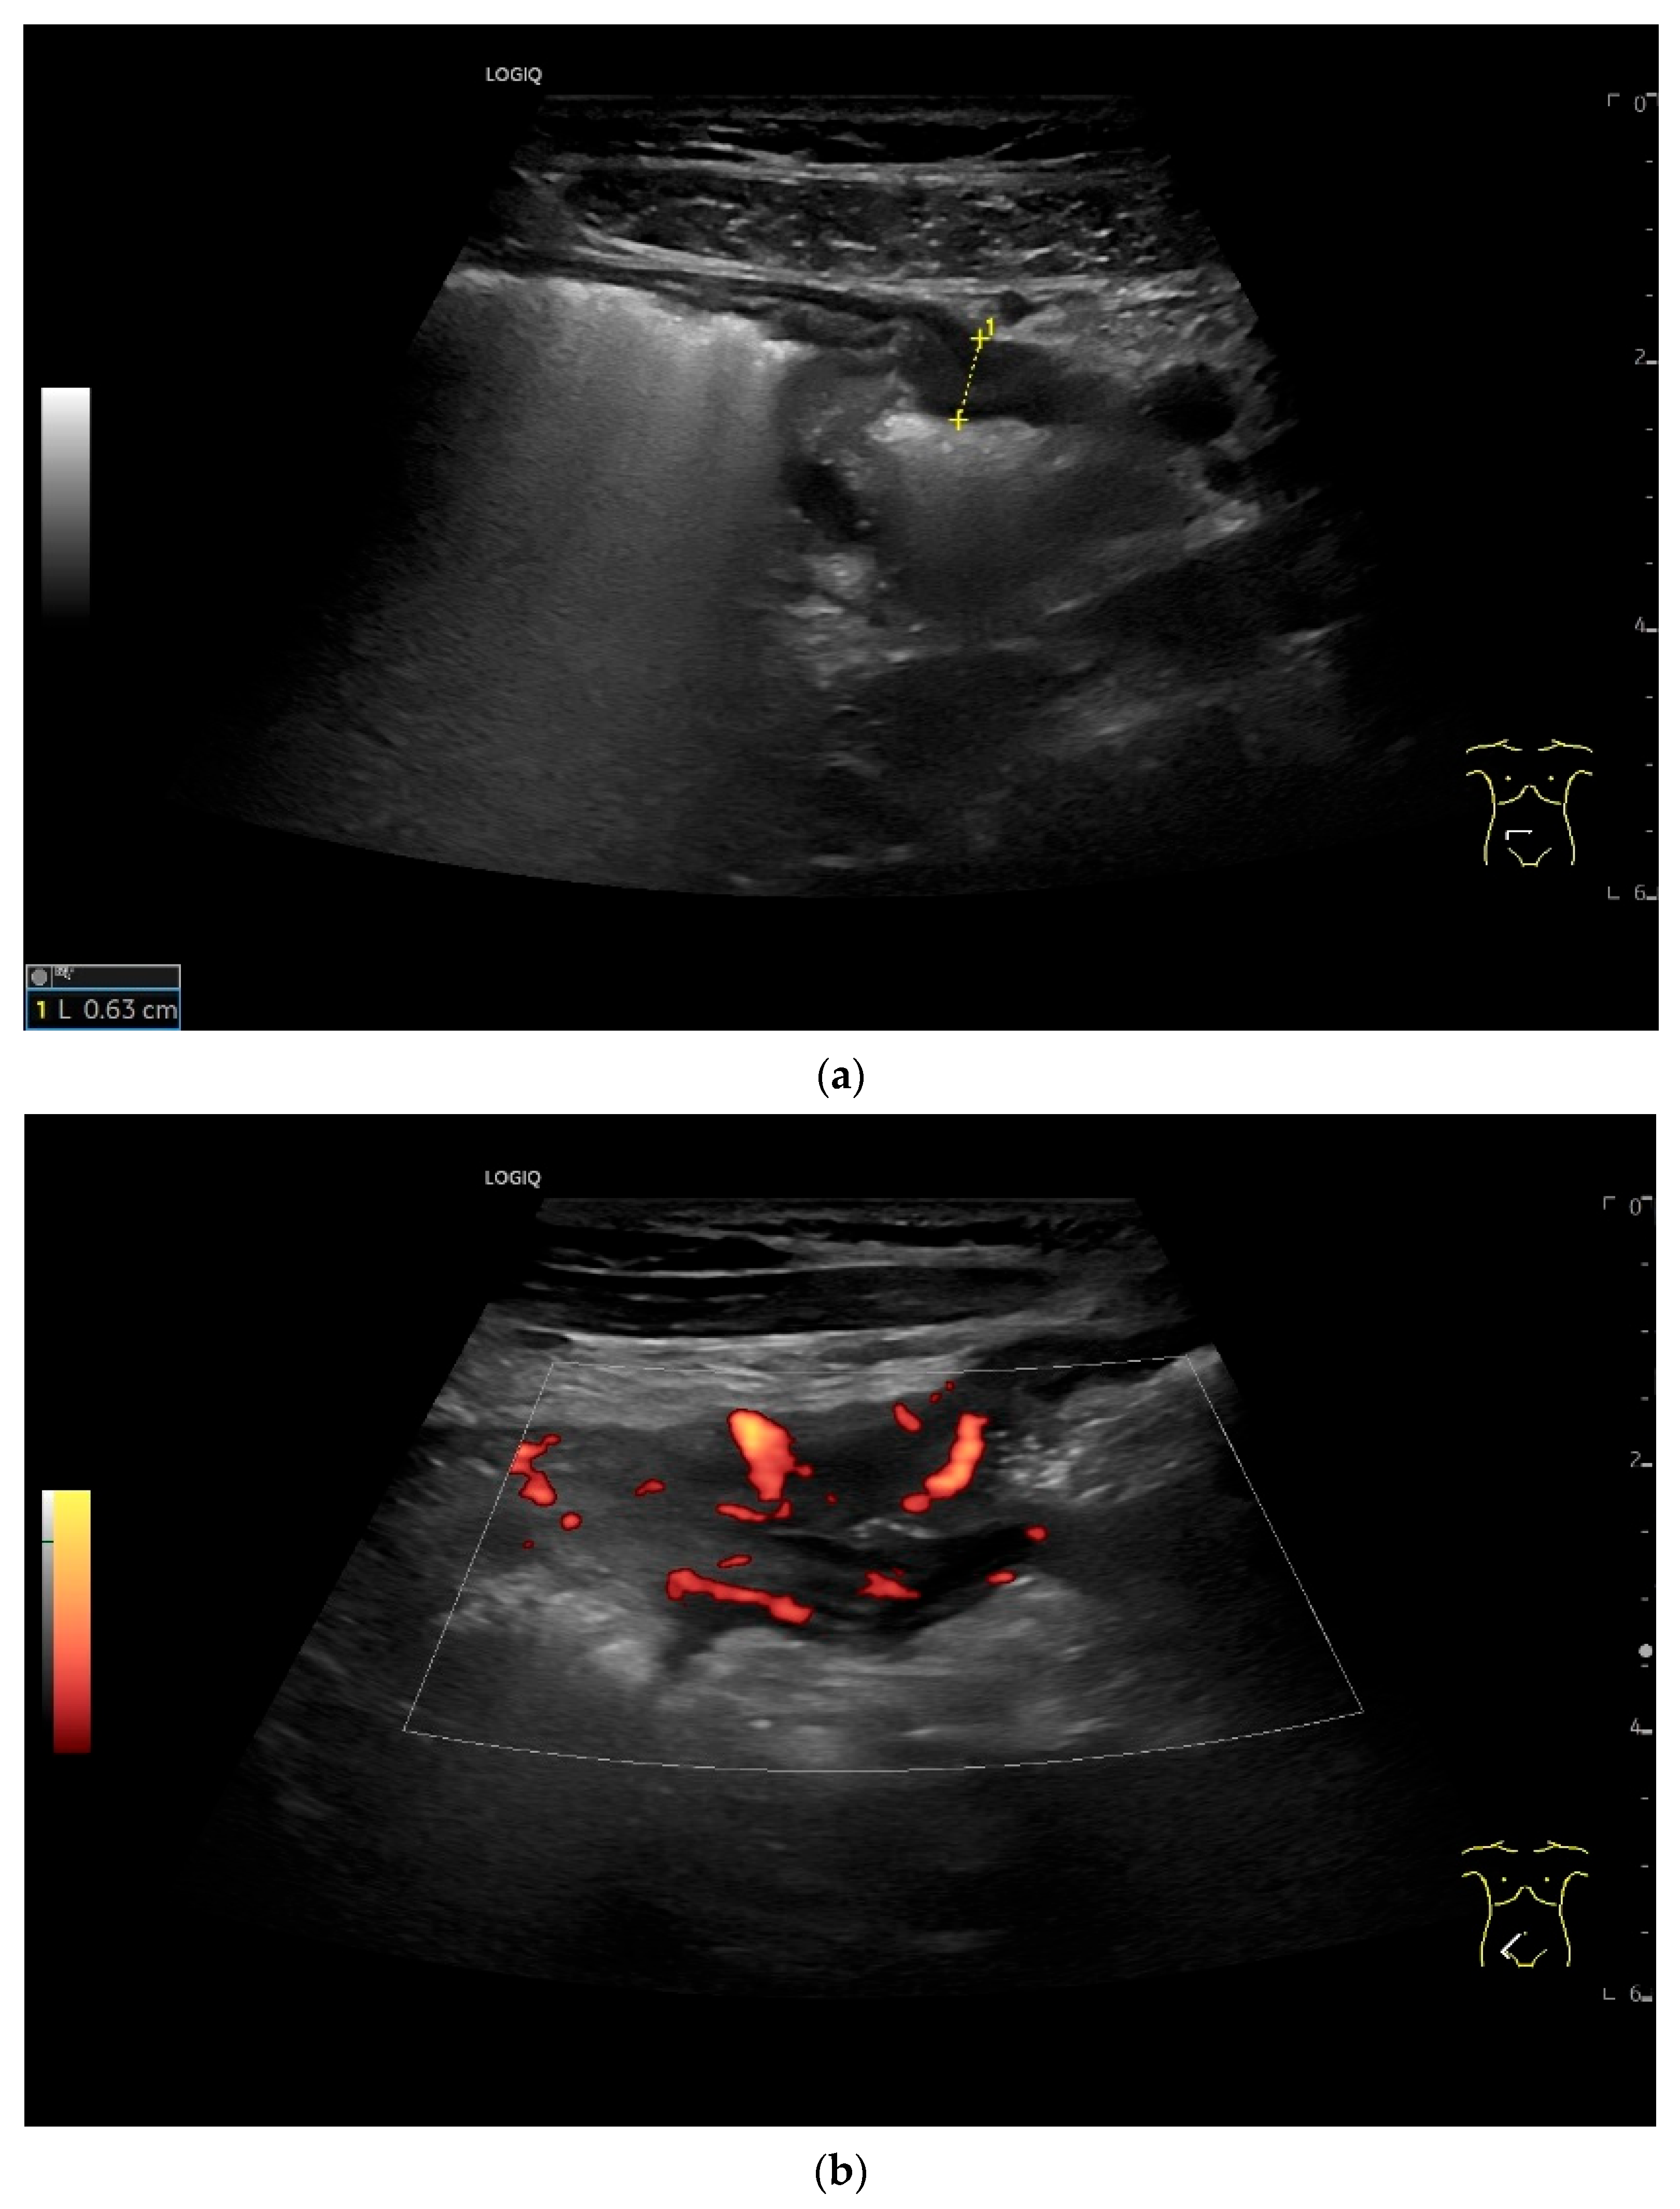

Figure 9.

Burkitt-Lymphoma. In a patient with weight loss, increased abdominal circumference, anemia, and physical weakness, the initial sonographic examination reveals an extensive tumor with intense hypoechogenicity and a connection to the jejunum in the left mid-abdomen. Despite its pronounced hypoechogenicity, a feeding vessel on CDI indicates a solid character (a). The tumor significantly thickens the wall and is intensely hypoechoic. The arrows point to the multisegmental hypoechoic wall thickenings (b). Normal wall structures are still visible (W), and the tumor extends beyond the wall (arrow) (c). In addition to delicate Kerckring folds (KF), there are significantly polypoid thickened KF with pronounced hypoechogenicity (d). The thickening of KF is very extensive (e). Wall thickening was found also in the stomach and colon and allowed endoscopic biopsy to establish the diagnosis.